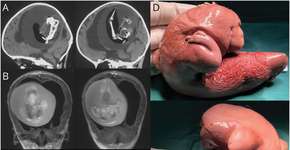

Mulher descobre síndrome rara após comer hambúrguer